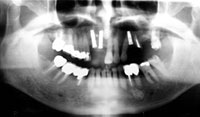

インプラント埋入後のパノラマ写真

2.インプラント治療(1次手術)骨再生療法

(上顎のインプラントの場合は骨とインプラントが完全にくっつくまで約6ケ月の期間をあける。下顎の場合は約3ケ月)

3.骨がくっついている6ケ月の間に全体の咬合改善(全体に被せ物をし、高さを上げる)

4.6ケ月後、骨とインプラントが完全にくっつき馴染んでから2次手術にて被せ物を入れる(インプラント治療完了)